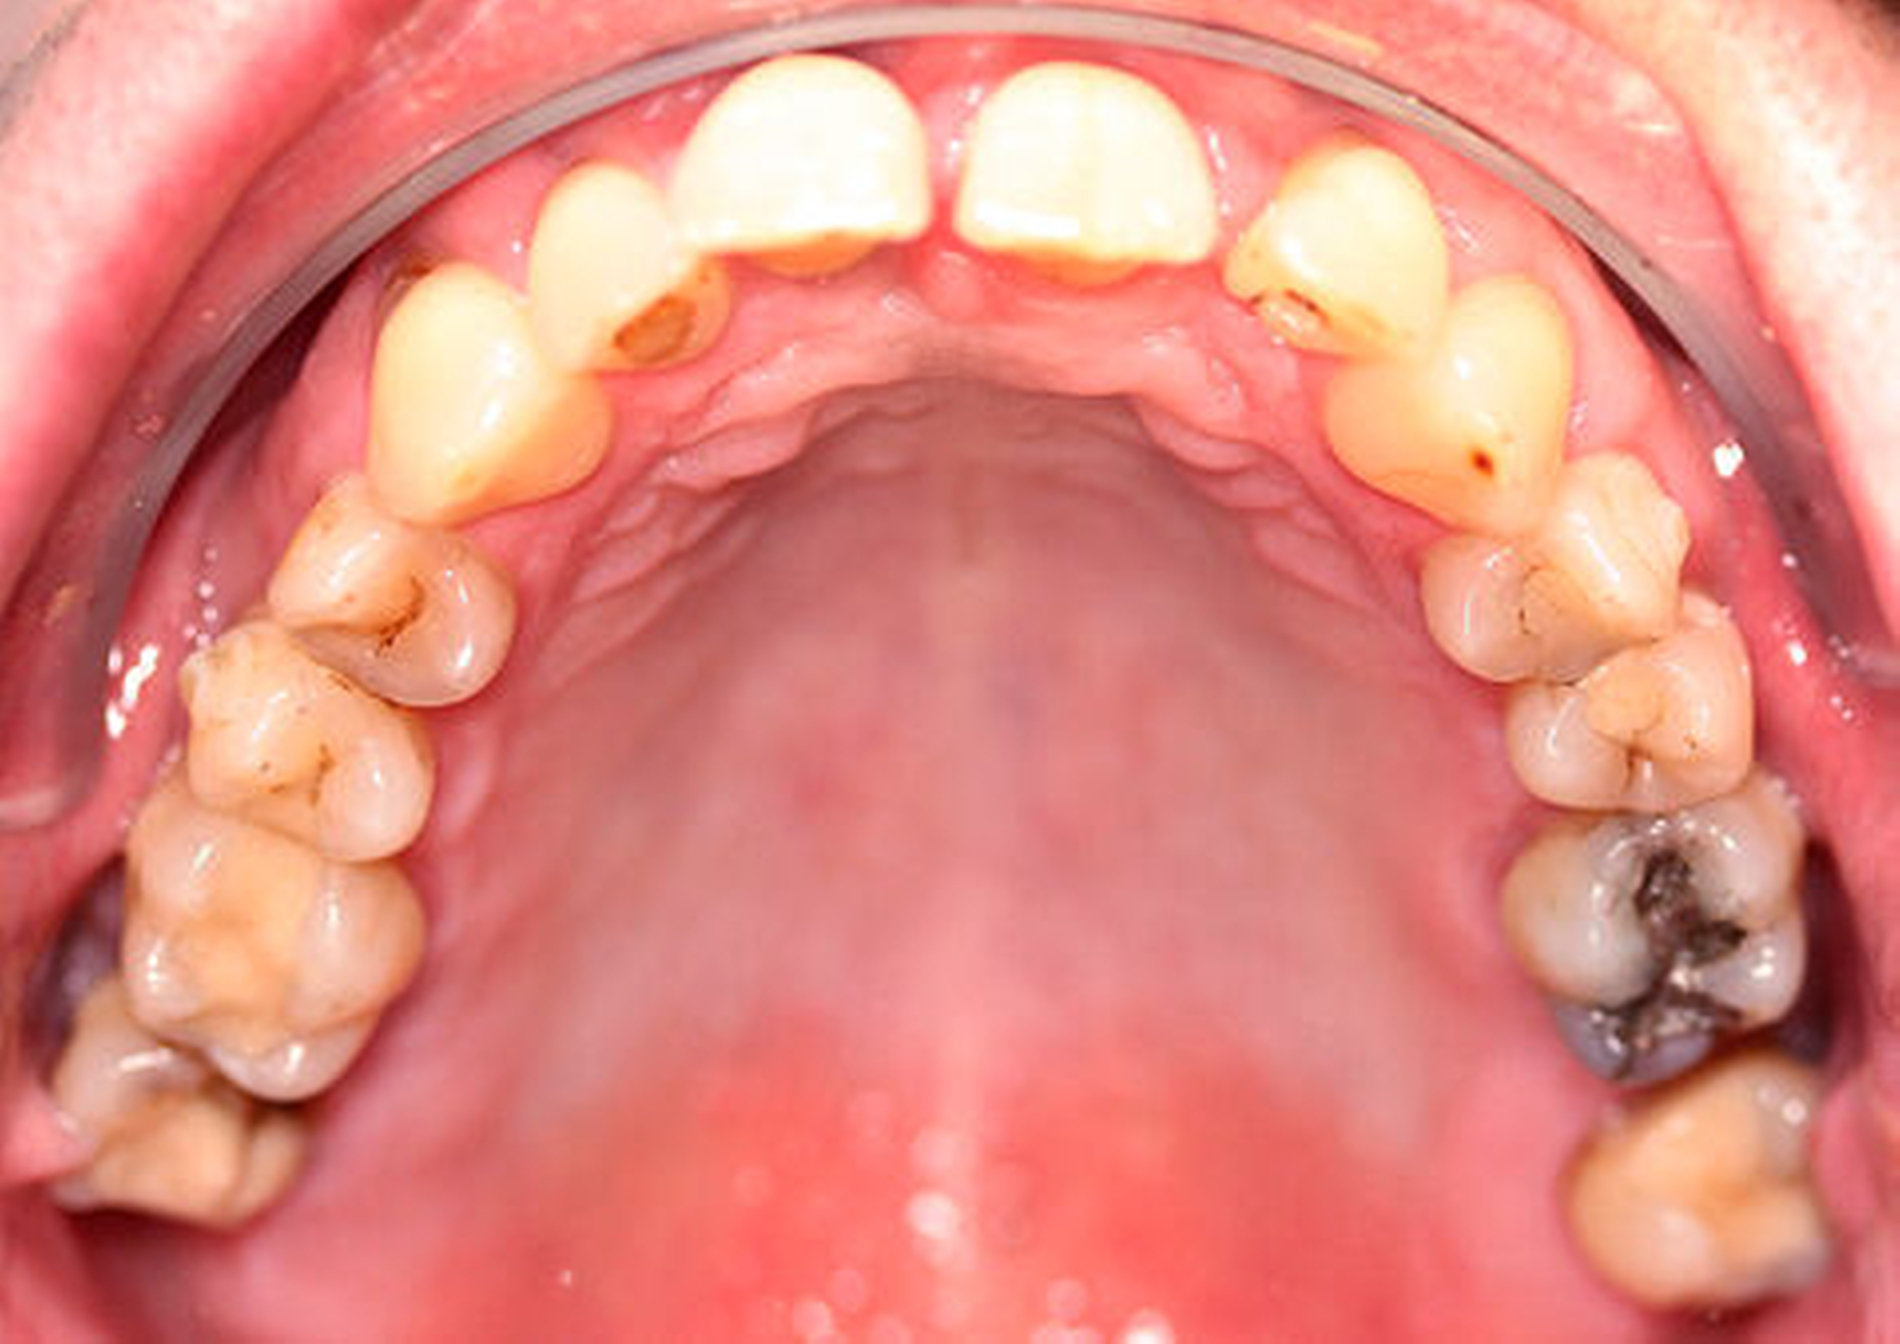

Röntgenologisch stellte sich im Orthopantomogramm der bereits intraoral ersichtliche horizontale und vertikale Knochenabbau mit Attachmentverlust an einzelnen Zähnen dar. Die Erhaltungswürdigkeit einzelner Zähne war aufgrund des starken Knochenverlustes beziehungsweise der Beeinträchtigung des Halteapparates als kritisch zu beurteilen.

Zudem wurde die Diagnose einer Parodontitis gestellt, die eine Rücküberweisung an den Hauszahnarzt erforderlich machte (Abbildung 2).